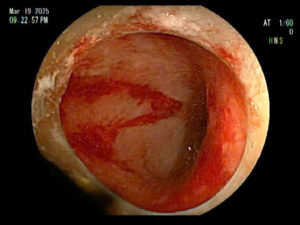

Vừa qua, Bệnh viện Đa khoa Bố Hạ tiếp nhận bệnh nhân đến khám trong tình trạng đau bụng âm ỉ, đầy chướng bụng khó chịu, rối loạn đại tiện, chủ yếu là đại tiện phân lỏng. Sau khi được thăm khám và nội soi đại tràng phát hiện ổ loét nông, bề mặt loét có máu tươi. Qua hình ảnh nội soi bệnh nhân được chẩn đoán viêm loét đại trực tràng chảy máu. Các biến chứng của viêm loét đại trực tràng đều tương đối nguy hiểm, có thể ảnh hưởng trực tiếp đến sức khỏe, tính mạng của người bệnh.

Nội soi đại tràng có giá trị cao trong chẩn đoán. Ống nội soi mềm quan sát mọi ngóc ngách bên trong ống tiêu hóa giúp phát hiện những bất thường và bệnh lý gặp phải dù là giai đoạn rất sớm.